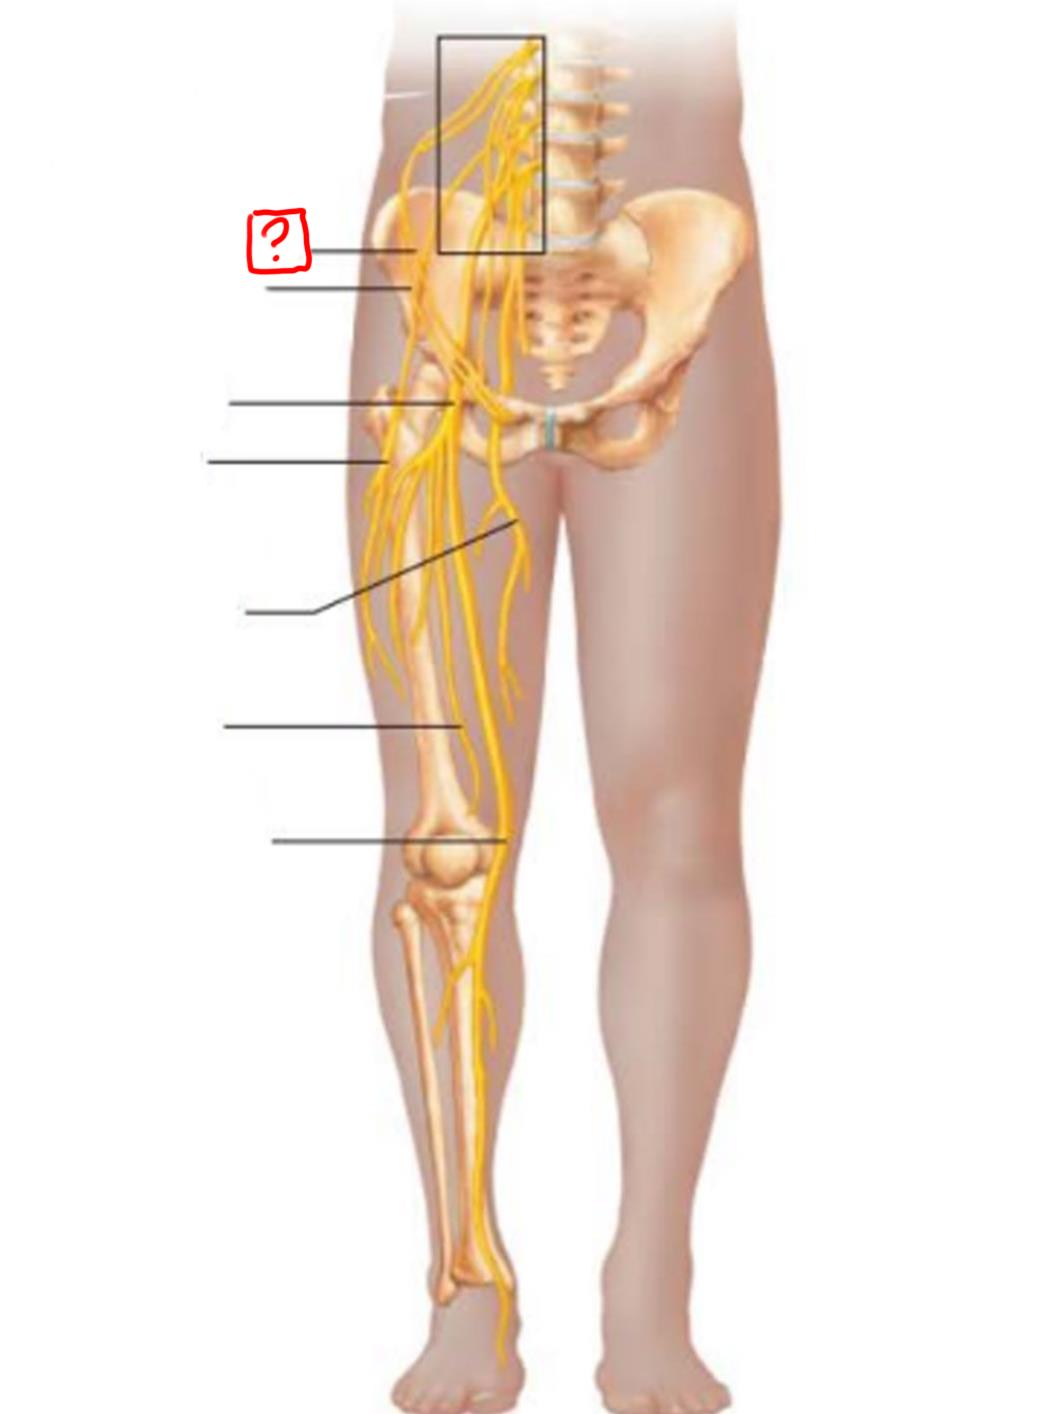

iliohypogastric

ilioinguinal

genitofemoral

lateral femoral cutaneous

obturator

femoral

lumbosacral trunk